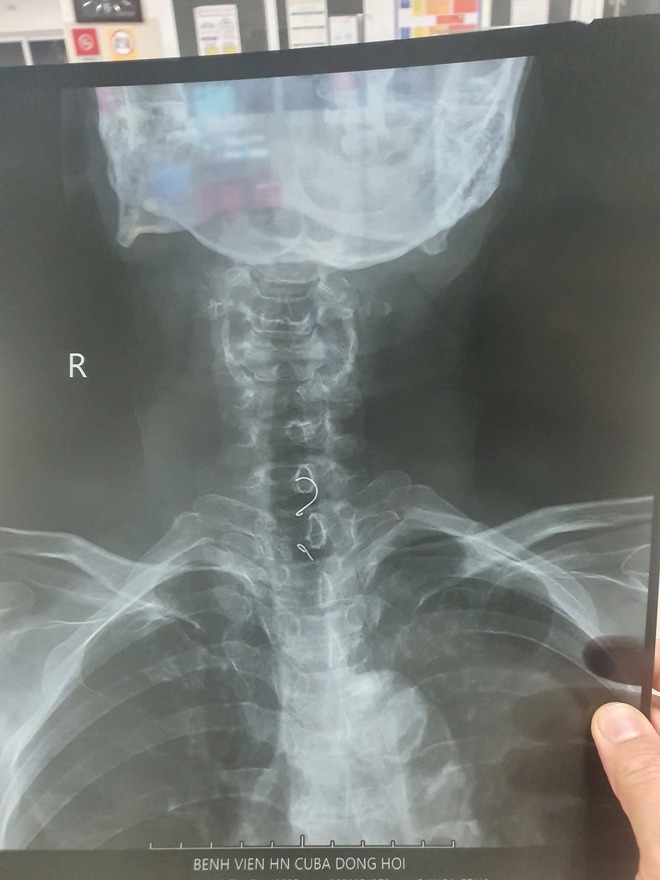

Không chỉ ở trẻ nhỏ, các ca hóc dị vật ở người lớn cũng diễn ra khá phổ biến với nhiều tình huống bất ngờ. Tại khoa Nội tiêu hóa - Huyết học lâm sàng (Bệnh viện hữu nghị Việt Nam - Cu Ba Đồng Hới), thời gian qua liên tục tiếp nhận các ca dị vật thực quản.

Đáng chú ý, ngày 19.1, các bác sĩ tiếp nhận một ca xuất huyết tiêu hóa nôn ra máu, đồng thời nhận thông tin về bệnh nhân đau thắt ngực dữ dội. Qua chẩn đoán hình ảnh, phát hiện dị vật nghi đâm xuyên cơ thực quản. Sau hội chẩn liên khoa và phối hợp giữa các chuyên khoa tim mạch, ngoại tổng hợp, ê kíp đã nội soi gắp thành công một chiếc xương cá dài gần 7 cm, đảm bảo an toàn cho người bệnh.

Thầy thuốc ưu tú, bác sĩ chuyên khoa 2 Nguyễn Duy Thạch, Trưởng khoa Nội tiêu hóa - Huyết học lâm sàng (Bệnh viện hữu nghị Việt Nam - Cu Ba Đồng Hới), cho biết thực quản có 5 đoạn hẹp sinh lý, dễ khiến dị vật mắc kẹt. Thống kê cho thấy dị vật thường dừng lại ở vùng cổ (74%), đoạn ngực (22%) và đoạn dưới ngực (4%).